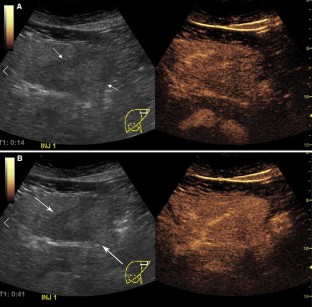

Fig. 1